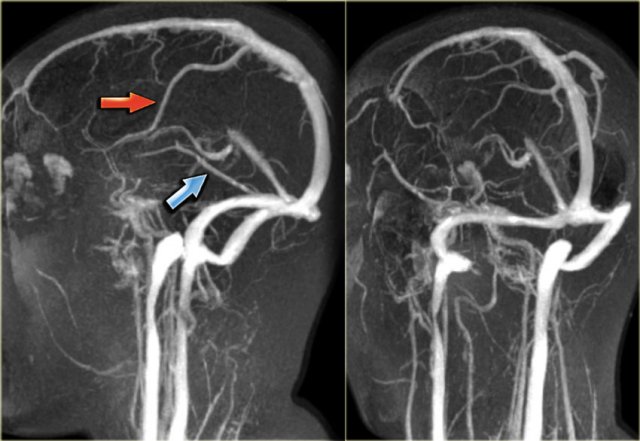

Why is CTA especially useful in acute ischemic stroke?

It identifies the site of vessel occlusion by showing the abrupt cessation of contrast in the affected artery.

What is a Maximum Intensity Projection (MIP)?

A reconstruction technique that displays only high HU voxels to enhance visualization of contrast-filled vessels.

Why are MIPs essential for CTA interpretation?

They remove low-attenuation tissue and highlight vascular anatomy.

What does a hyperdense MCA sign indicate?

An occlusive thrombus in the middle cerebral artery.

Should CTA proceed if a hyperdense artery is seen but no bleed is present?

Yes.